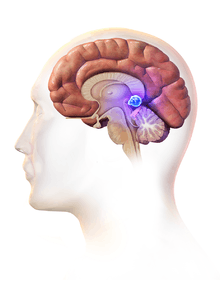

Diagram of the pineal gland in the human brain. The pineal gland is where the Papillary Tumor is located. | |

Papillary tumors of the pineal region (PTPR) were first described by A. Jouvet et al. in 2003 [1] and were introduced in the World Health Organization (WHO) classification of Central Nervous System (CNS) in 2007.[2] Papillary Tumors of the Pineal Region are located on the pineal gland which is located in the center of the brain. The pineal gland is located on roof of the diencephalon. It is a cone shaped structure dorsal to the midbrain tectum.[3] The tumor appears to be derived from the specialized ependymal cells of the subcommissural organ.[1][4][5] Papillary tumors of the central nervous system and particularly of the pineal region are very rare and so diagnosing them is extremely difficult.[6]